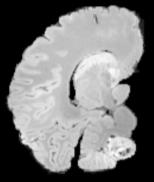

In neuroimaging, MRI tissue properties characterize underlying neurobiology, provide quantitative biomarkers for neurological disease detection and analysis, and can be used to synthesize arbitrary MRI contrasts. Estimating tissue properties from a single scan session using a protocol available on all clinical scanners promises to reduce scan time and cost, enable quantitative analysis in routine clinical scans and provide scan-independent biomarkers of disease. However, existing tissue properties estimation methods - most often $\mathbf{T_1}$ relaxation, $\mathbf{T_2^*}$ relaxation, and proton density ($\mathbf{PD}$) - require data from multiple scan sessions and cannot estimate all properties from a single clinically available MRI protocol such as the multiecho MRI scan. In addition, the widespread use of non-standard acquisition parameters across clinical imaging sites require estimation methods that can generalize across varying scanner parameters. However, existing learning methods are acquisition protocol specific and cannot estimate from heterogenous clinical data from different imaging sites. In this work we propose an unsupervised deep-learning strategy that employs MRI physics to estimate all three tissue properties from a single multiecho MRI scan session, and generalizes across varying acquisition parameters. The proposed strategy optimizes accurate synthesis of new MRI contrasts from estimated latent tissue properties, enabling unsupervised training, we also employ random acquisition parameters during training to achieve acquisition generalization. We provide the first demonstration of estimating all tissue properties from a single multiecho scan session. We demonstrate improved accuracy and generalizability for tissue property estimation and MRI synthesis.